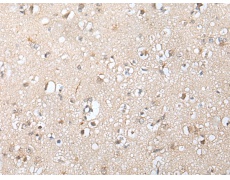

ELISA, IHC

IHC positive control:

Human brain and human gastric cancer